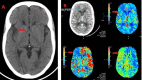

Since the coronavirus (COVID-19) pandemic started, new challenges have emerged regarding the management of coronavirus-infected patients. One of the most known devastating complications associated with COVID-19 is hypercoagulability. This can lead to severe disability or even death, especially in critically ill patients with known chronic comorbidities such as hypertension (HTN) and diabetes. D-dimer and clinical condition are among the most important tools currently used by clinicians to guide therapy and anticoagulation prophylaxis. Here we present a case of a COVID-19-infected patient with no known comorbidities and mild elevation in initial D-dimer level who had a rapid deterioration ultimately leading to death within weeks of admission.